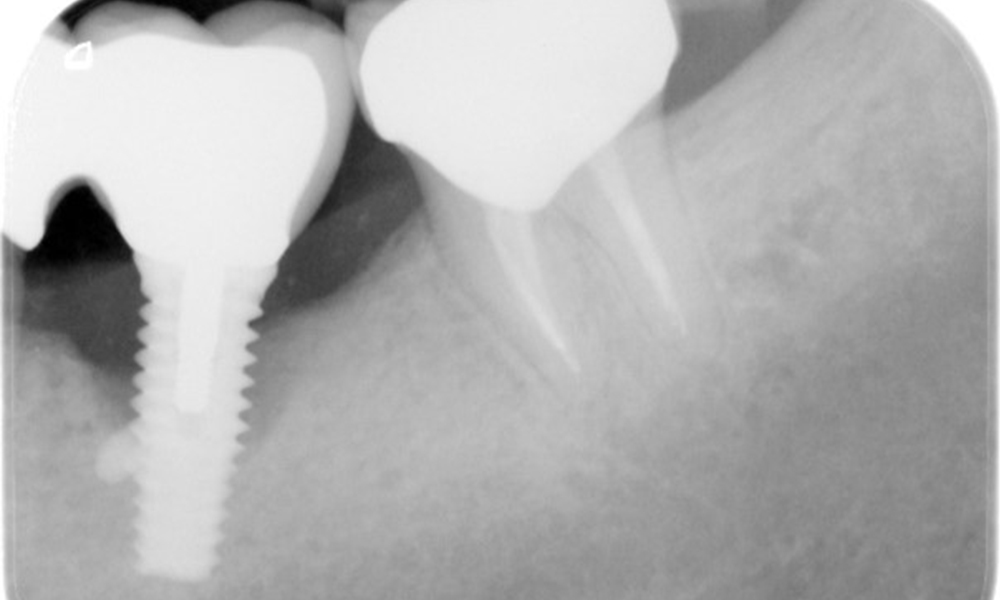

The X-ray images show the progression of bone loss.

The X-ray images show the progression of bone loss. OPG from 29.06.2020 (left) and OPG from 26.02.2024 (right).

OPG: 26/02/2024 Dental X-ray: 18/01/2024

The X-ray images show the progression of bone loss in the area of the implant in region 36: dental film from 11.02.2021 (left) and dental film from 18.01.2024 (right).